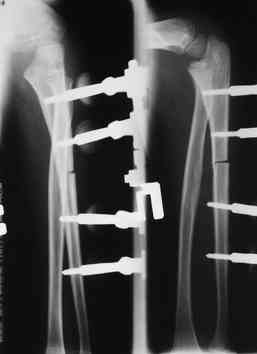

Артротомия, иссечение рубцов, остатков кольцевидной связки. На проксимальный отдел локтевой кости стержневой аппарат (рекомендуют

Compact II выпущеный Stryker Howmedica, но за неименеем...), остеотомия проксимального отдела локтевой кости, вправление головки лучевой кости, замыкание аппарата, проверка стабильности головки

лучевой кости в движении, ушивание без пластики кольцевидной связки.

Данную методику применили впервые. После артролиза очевидная нестабильность головки луча. После остеотомии локтевой, вправления и

стабилизации аппарата головка луча при движениях на месте. Первые впечатления- "Либо чудо,либо фокус" (с) :))

У нас были проблемы. Скорее всего связанные с использованием стержневого аппарата с простым соединением. В Компакте же скорее всего шарнирное, со свободой движения во всех плоскостях, что конечно, значительно должно упрощать фиксацию в правильном положении.

1 подвывих головки лучевой кости в положении супинации - через 2 недели после операции- под ЭОП: аппарат разблокирован, повторное вправление головки, стабилизация аппарата.